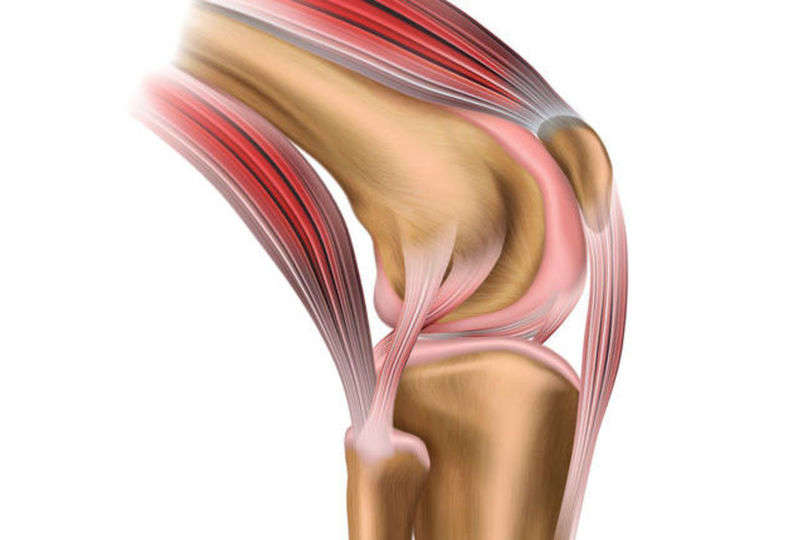

膝関節には大腿骨と脛骨をつなぐ靭帯が4本あります。そのうち、膝の前方や内側への回旋の動きを制動する靭帯が前十字靭帯(ACL)です。前十字靭帯は急激なストップや方向転換、ジャンプの着地で膝に剪断力が加わった時に脛が前方にずれることを防ぎ、スポーツを行う上で大切な靭帯になります。